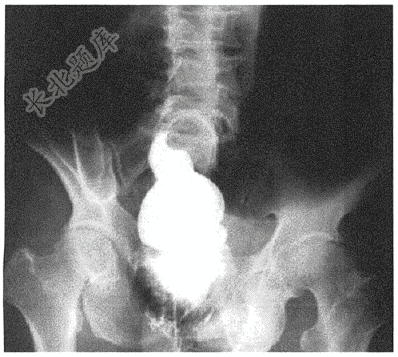

- 单项选择题患者老年女性,60岁,因突发腹痛腹胀,肛门停止排便排气2天入院。患者5年前因子宫肌瘤行腹腔镜辅助子宫切除术,术后无特殊不适。入院后行钡灌肠,图片如下( )

D、乙状结肠扭转